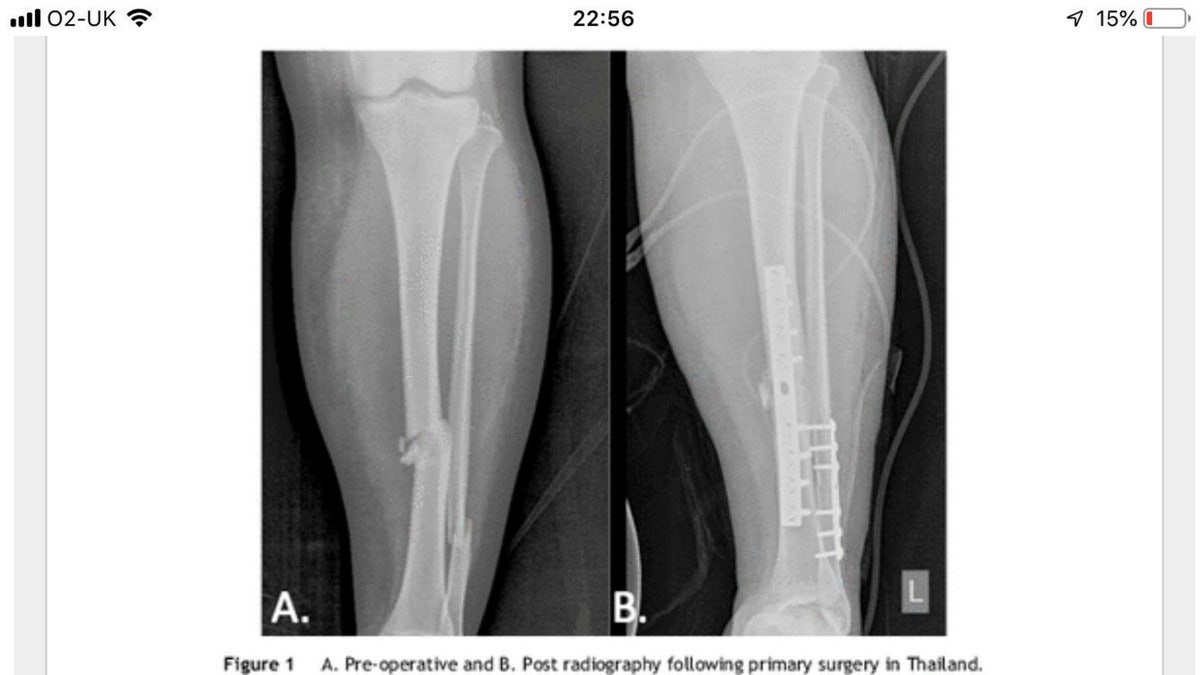

The impact reportedly broke Fitzpatrick’s tibia and fibula, and she was loaded into the back of a pick-up truck and rushed to an emergency room, which then transferred her to a hospital in Phuket. Fitzpatrick told the news outlet that her first surgery involved inserting pins into her leg to fix the broken bone, but that she had developed complications with her skin.

She said surgeons cut away dead skin, which left a gaping hole in her leg later filled with muscle taken from another area of her limb. (SWNS)

“Although the bones were mending, I had a hole in my leg where they had cut away the skin,” she told SNWS of her initial care. “You could see right to the metal work in my leg.”

She said the surgeon in the U.K. used muscle from another area of her leg to mend the gap in her limb, but that she was warned about the potential for rejection and need for amputation. She said that soon after that operation, they discovered she had an infection from a bacteria found in water that was preventing her healing, and that she also found out she was pregnant.